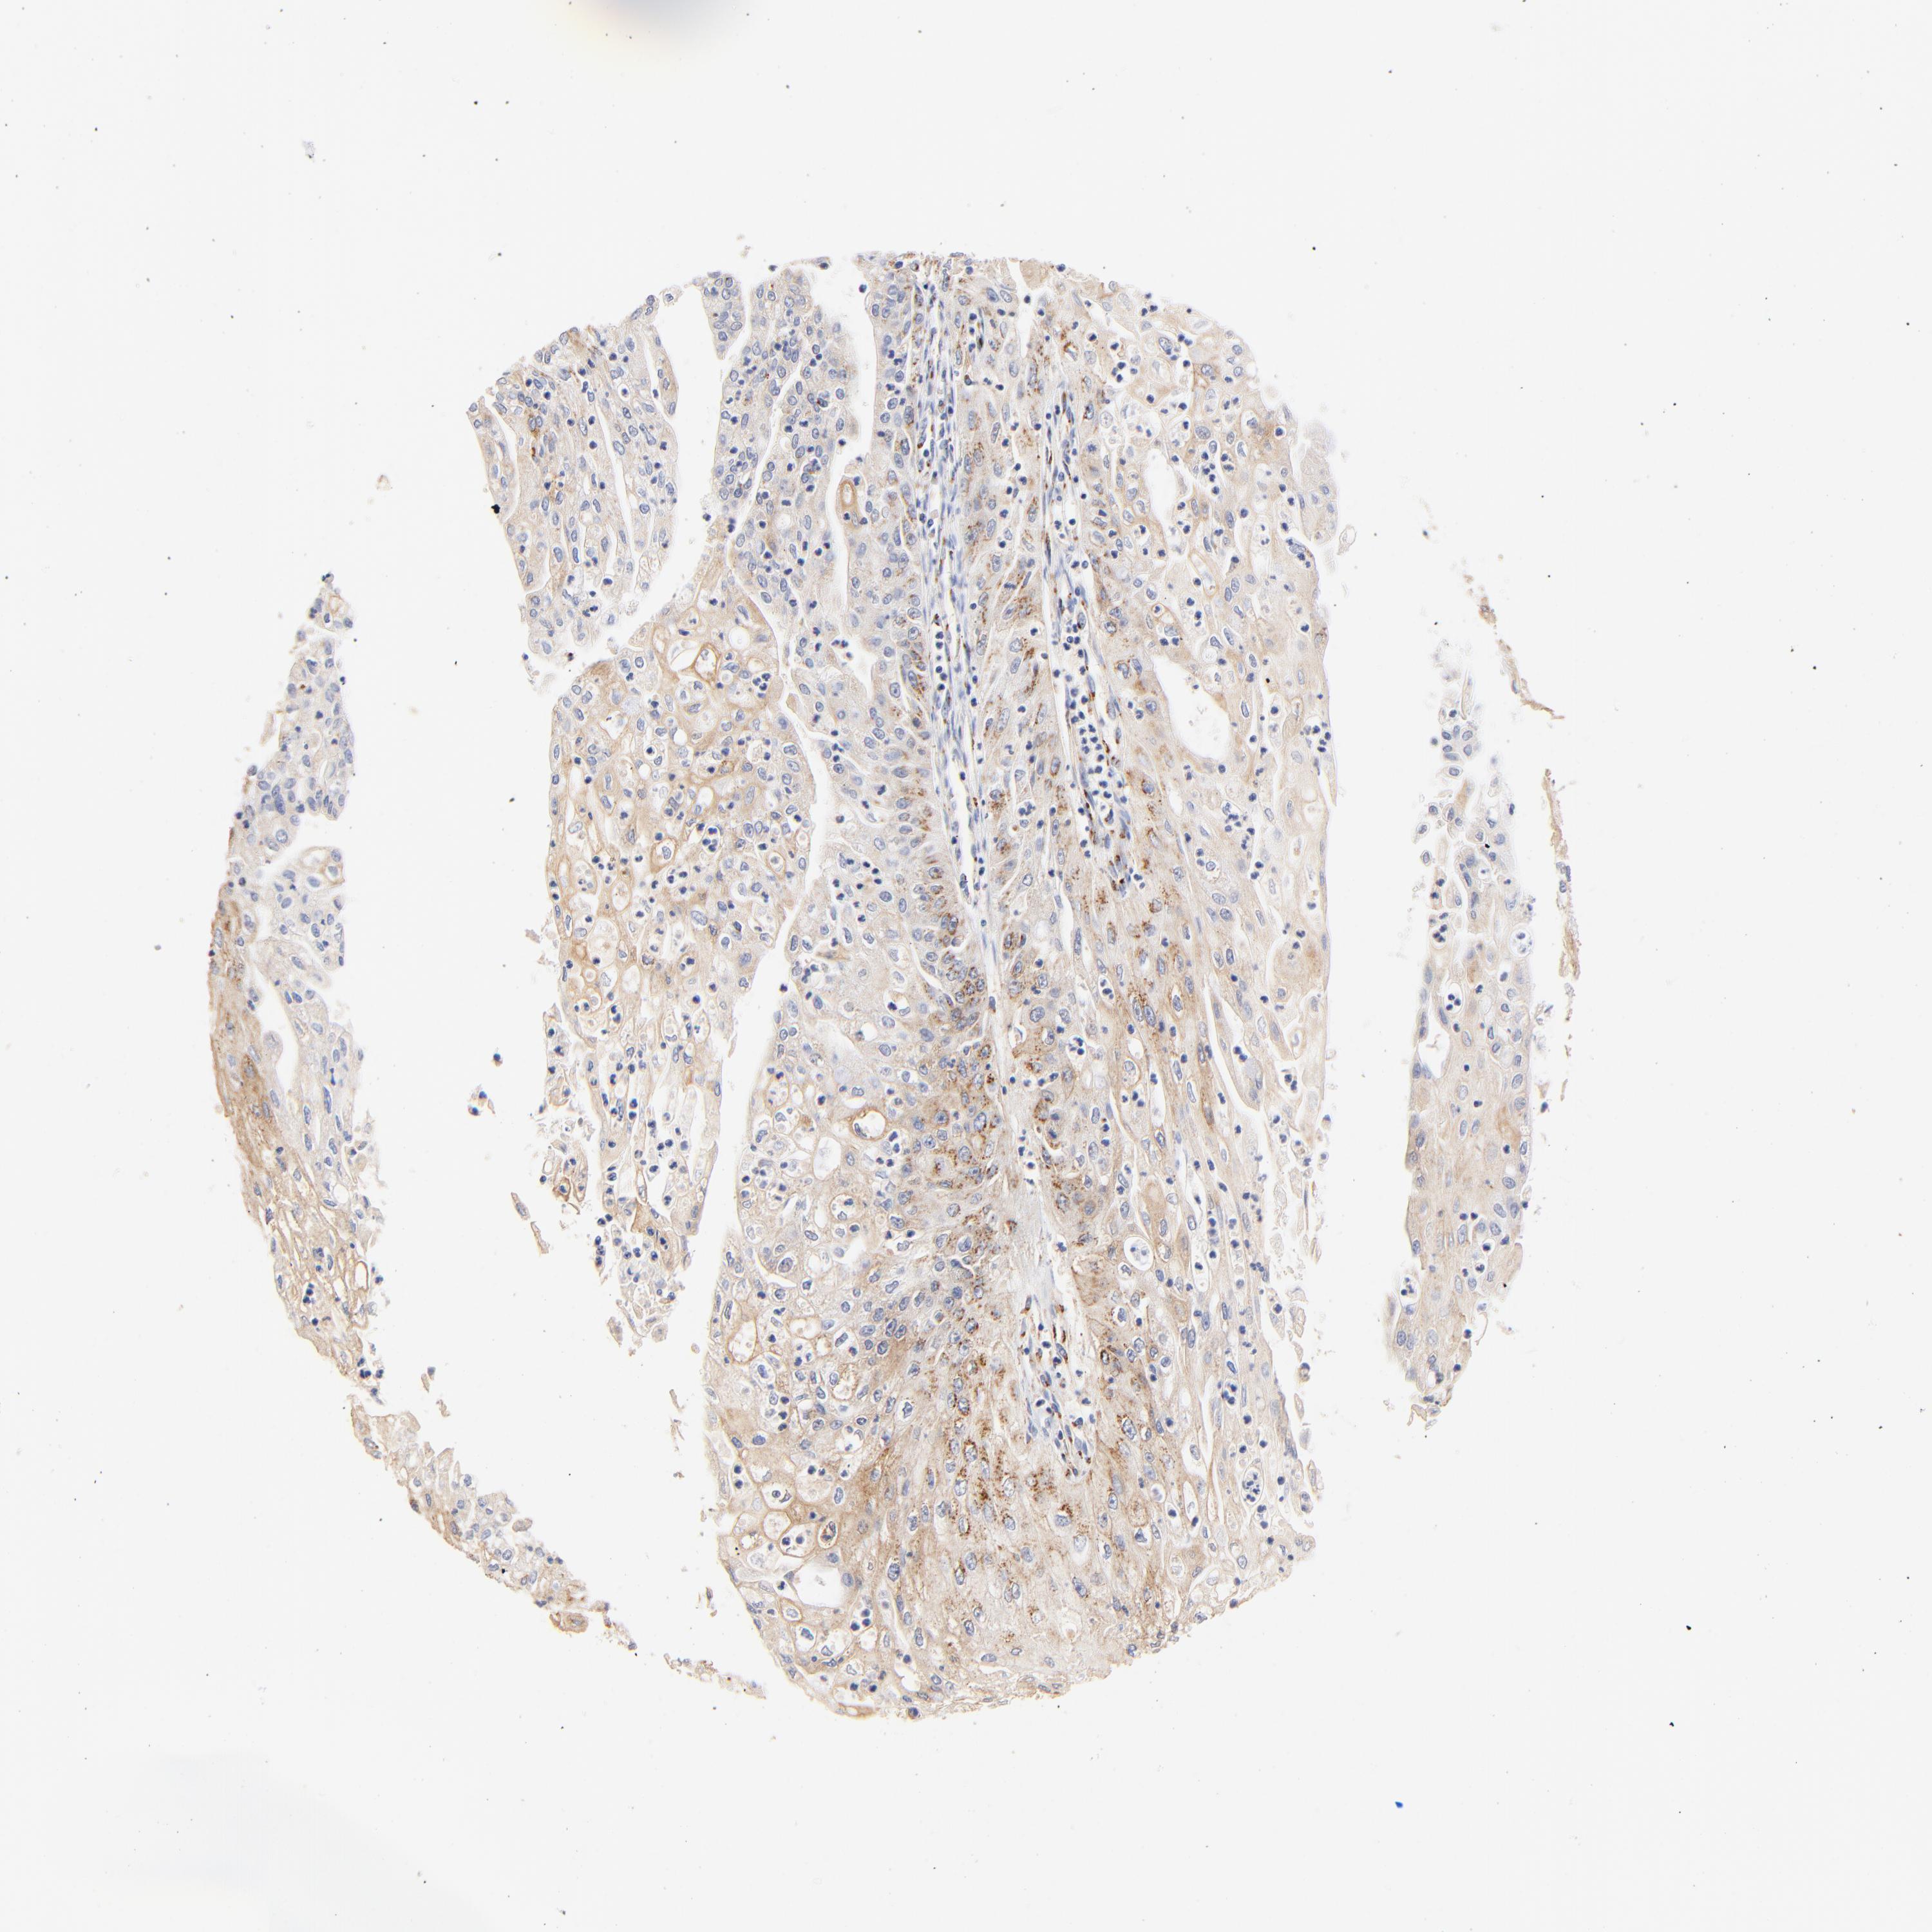

ENDOMETRIAL CANCER - Protein expressioni

A mouse-over function shows sample information and annotation data. Click on an image to view it in a full screen mode. Samples can be filtered based on level of antibody staining by selecting one or several of the following categories: high, medium, low and not detected. The assay and annotation is described here.

Note that samples used for immunohistochemistry by the Human Protein Atlas do not correspond to samples in the TCGA dataset.

Antibody stainingi

Antibody staining in the annotated cell types in the current human tissue is reported as not detected, low, medium, or high, based on conventional immunohistochemistry profiling in selected tissues. This score is based on the combination of the staining intensity and fraction of stained cells.

Each image is clickable and will lead to virtual microscopy that enables deeper exploration of all samples and also displays staining intensity scores, fraction scores and subcellular localization as well as patient and tissue information for each sample.

Antibody HPA002552

Staining

High

Medium

Low

Not detected

Intensity

Strong

Moderate

Weak

Negative

Quantity

>75%

75%-25%

<25%

None

Location

Nuclear

Cytoplasmic/membranous

Cytoplasmic/membranous,nuclear

Adenocarcinoma, NOS